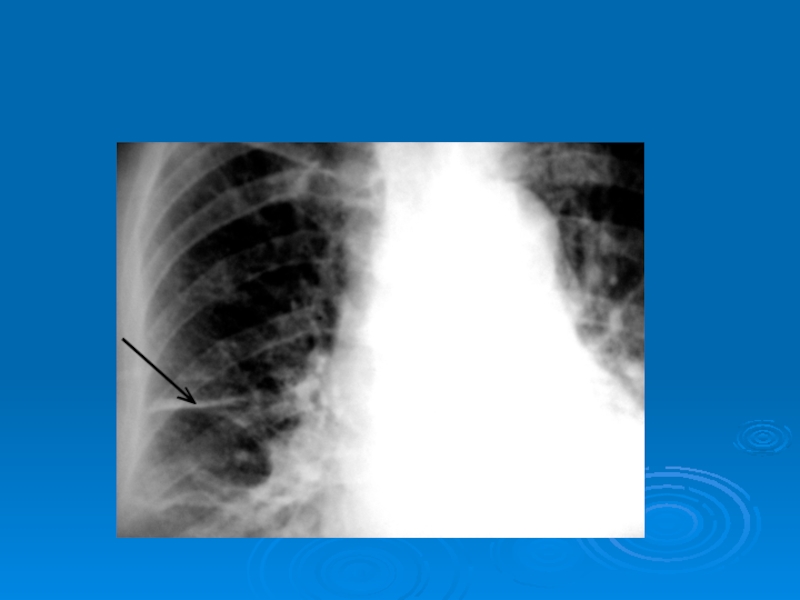

Слайд 44Рентгенограммы больных с абсцессами в правом и левом легком

Рентгенограммы больных с абсцессами в правом и левом легком